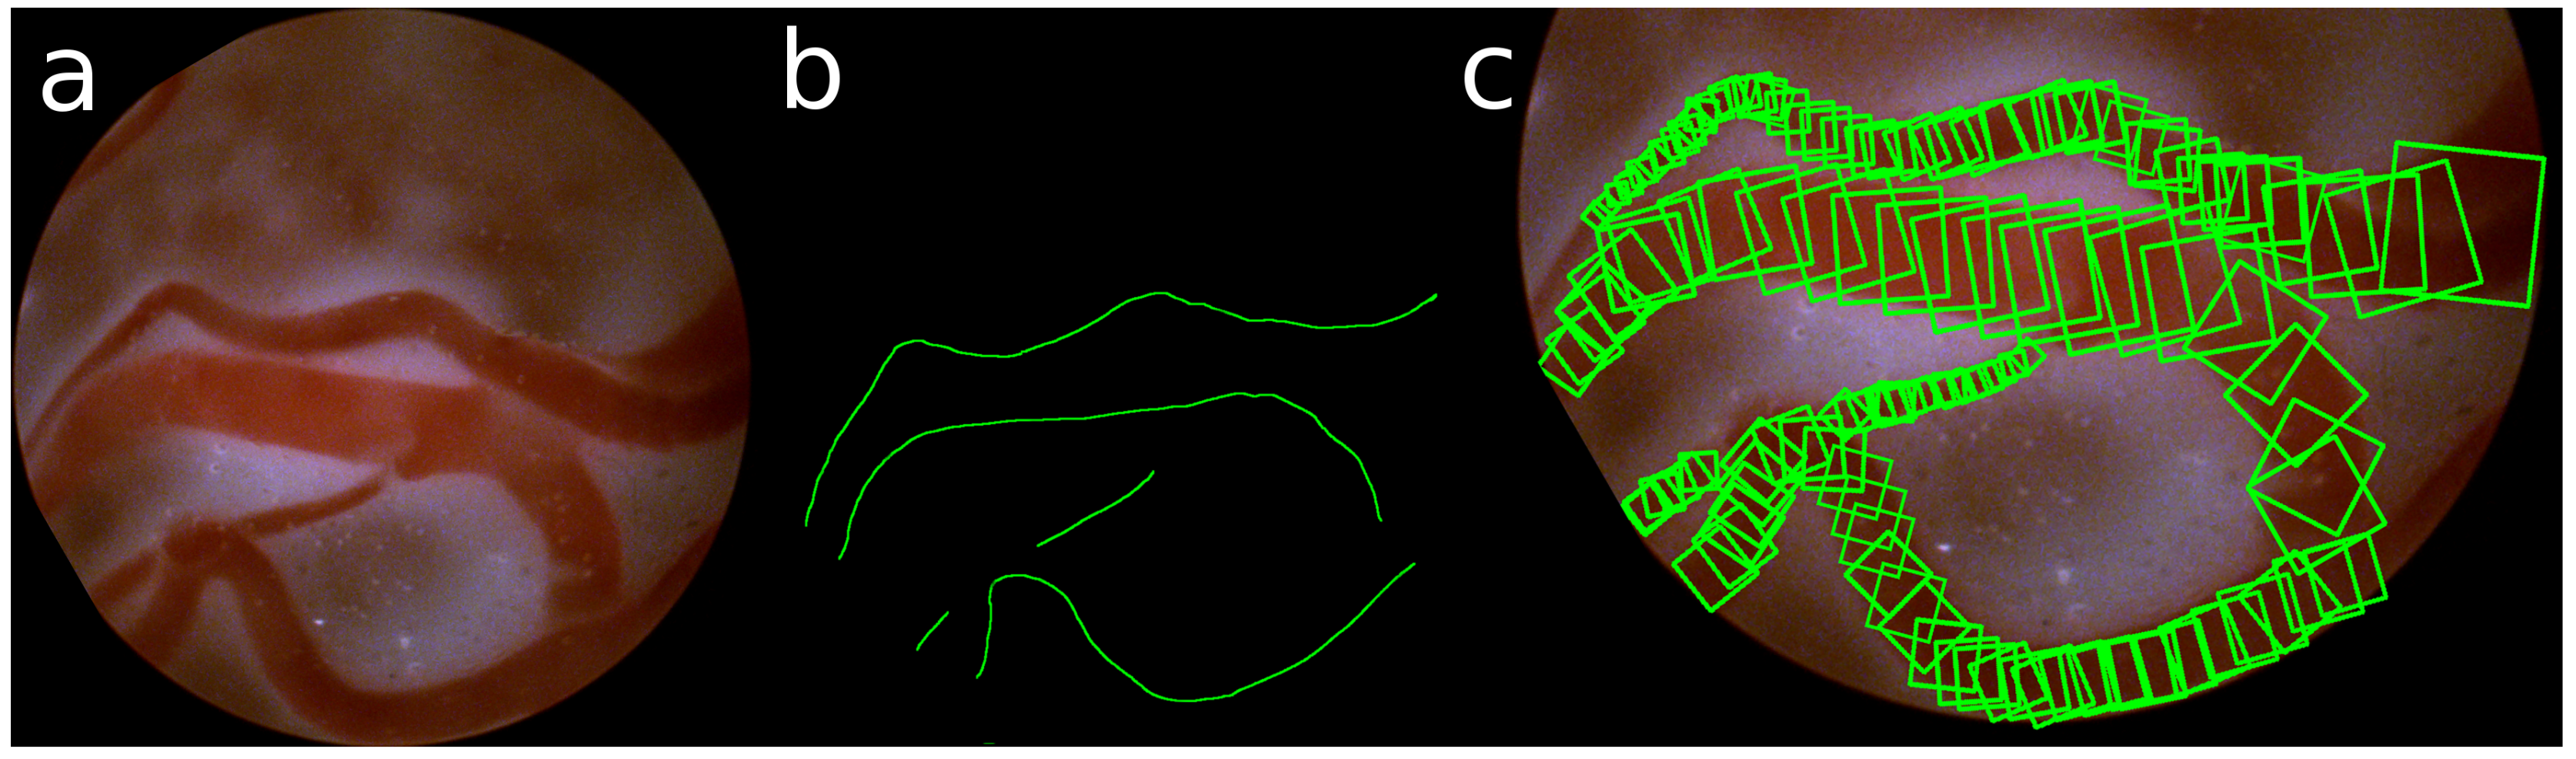

The ground truth of these detections is obtained by manually annotating the center and the radius of the veins in the images. Taking the gradient of these annotations, also the direction of the vein is defined. An example of such annotation of the veins is shown in Figure 5.

The stable region detector as proposed in Section 3.1 should detect the center of the vein. Therefore, we manually annotated the center and the radius of the veins and extracted the direction of the veins. According to the chosen scales and number of cells in the convolutional layers, the closest annotated point is selected as the ground truth and used to train the stable region detection network.

Figure 5. (a) Sample image; (b) annotated center line; (c) selection of annotated RBoxes.